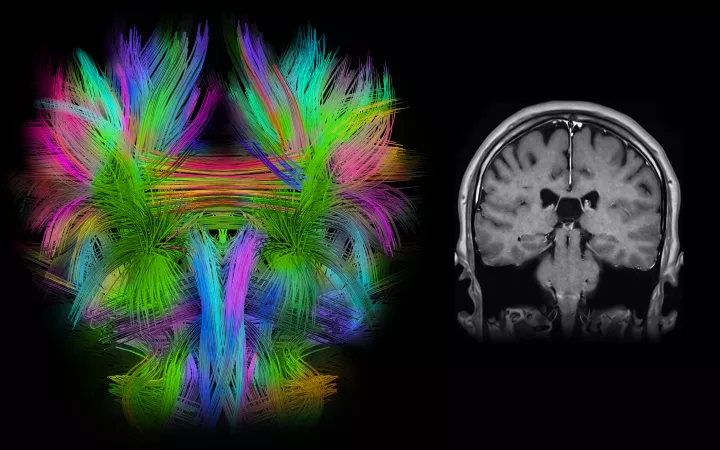

We utilize advanced technologies, including precise minimally invasive surgical placement of electrodes into brain areas uniquely involved in mediating specific movement disorders, along with subsequent programming and refinement of stimulation parameters to optimally treat individual conditions. We are ranked in the top 1% of all hospitals in the nation for neurology and neurosurgery, according to U.S. News & World Report, and an international referral site for complex and challenging movement disorder cases.

DBS is a surgical procedure that involves implanting electrodes into specific areas of the brain to help regulate abnormal brain activity and alleviate symptoms associated with PD. There are two FDA-approved targets for the treatment of PD: the Globus pallidus internus (GPi) and the subthalamic nucleus (STN). The decision to recommend surgery and identification of the target is made after a careful evaluation by an experienced movement disorders team. Patients being considered for DBS have a history of PD responsive to medications for 3-5 years.

Deep brain stimulation is a minimally invasive procedure that involves placement of one or two thin wires or electrodes into parts of the brain, or nuclei, that are known to have abnormal patterns of activity in particular movement disorders. The procedure is normally performed in two stages. In the first stage, electrodes are implanted into the GPi or the STN. This procedure is usually performed with the patient awake but lightly sedated to obtain appropriate neural recordings and to ensure that stimulation through the electrodes alleviates the symptoms. The second stage takes place one or two days later and consists of connecting the electrode wires to a small pulse generator (very similar to a pacemaker) which is implanted below the clavicle. This is a short procedure performed with anesthesia. After the surgery, the movement disorders neurologist adjusts the stimulation parameters, such as frequency, voltage, and pulse width, to achieve the best therapeutic effect with minimal side effects.

As with treatment for Parkinson’s disease, ET patients considering DBS should be thoroughly evaluated by a team of specialists, including a movement disorders neurologist, and neuropsychologist and a specialized neurosurgeon. A high-quality MRI–used to ensure that there are no significant brain abnormalities–is an important element of surgical planning. DBS involves implanting electrodes into a nucleus called the thalamus to help regulate abnormal brain activity and alleviate symptoms associated with ET. There is only one established and FDA-approved target for the treatment of ET, called the Ventralis intermedius nucleus (Vim), found within the larger thalamus.